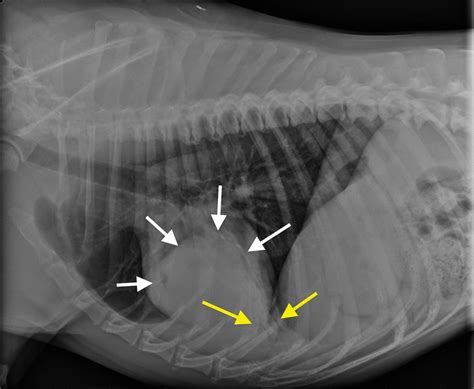

Chest X-rays

Chest X-rays provide a detailed image of the lungs and surrounding structures. They can help identify abnormalities such as inflammation, fluid accumulation, or tumors. X-rays are a non-invasive and relatively quick procedure, making them a valuable tool in diagnosing canine lung disease.